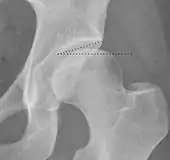

Projectional radiography ("X-ray")is often considered first line for FAI.[10] Anterior-posterior pelvis and a lateral image of the hip in question should be attained.[10] A 45-degree Dunn view is also recommended.[10][19]

| Tönnis angle | ![]() |

Slope of the sourcil (the sclerotic weight-bearing portion of the acetabulum) | 0 to 10°

|